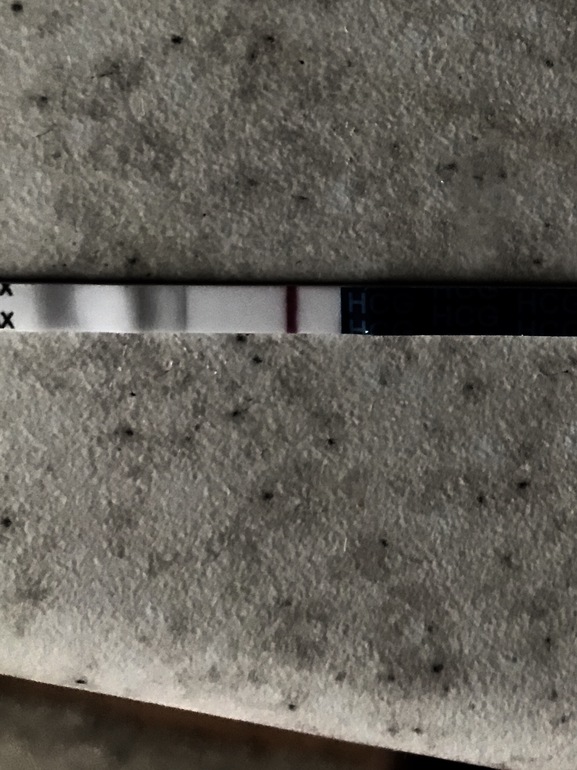

Вечером сделала Эвитест, появилась слабая полоска через минуту где-то, а после высыхания она пропала и тест остался отрицательный. И как это можно понять? Или это реагент такой на эвике?  Надеюсь ее будет видно, это мокрый.

Надеюсь ее будет видно, это мокрый.

И вот затемнила его, так лучше видно будет надеюсь.

Я вижу розовенькую полосочку

У меня такие всегда говорили о б.

Да, мне видно. Было и пропадала

Что-то там явно виднеется